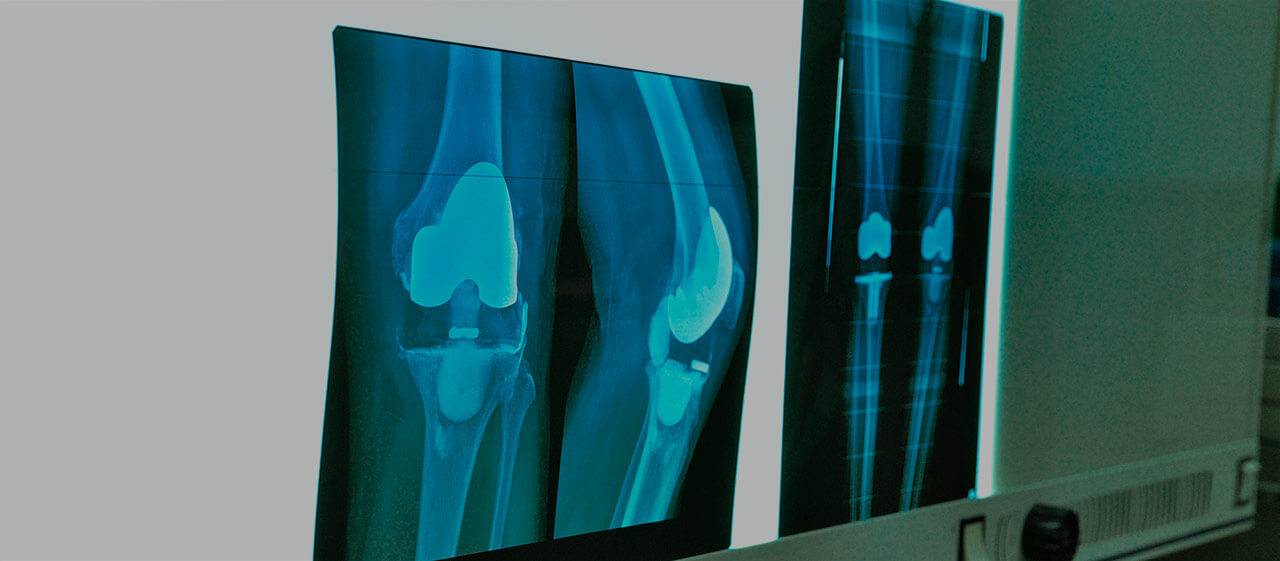

استبدال مفصل الركبة

تجرى عملية استبدال مفصل الركبة لدى معظم المرضى بإحدى الطرق الكلاسيكية ذات الفعالية المثبتة:

- استبدال المفصل الكلي أو الكامل، والذي يتضمن استبدال أجزاء مفصل عظم الفخذ والساق والغضروف داخل المفصل، والرضفة إذا لزم الأمر. نظراً للمتطلبات العالية لوظيفة مفصل الركب ، يتم إصلاح تثبيت الأطراف الاصطناعية في معظم الحالات باستخدام الأسمنت العظمي.

- استبدال المفصل الجزئي أو أحادي القطب، والذي غالباً ما يتضمن استبدال الجزء الإنسي (الداخلي) من الركبة. كقاعدة عامة، لا تتأثر الأربطة المفصلية والغضاريف في هذه الحالة. نظراً لصغر حجم العملية وصغر حجم الأطراف الاصطناعية، يتم إجراء التدخل بالمنظار.

- استبدال رضفة الركبة (رأب المفصل الرضفي الفخذي) - يتضمن استبدال الجزء الداخلي من الرضفة عند وجود آفة معزولة. يشار إلى رأب المفصل الفخذي الرضفي عند الغياب التام لعلامات التهاب المفاصل أو أي عملية مرضية في باقي أجزاء المفصل.